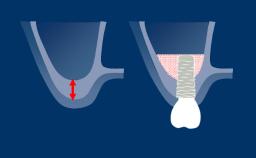

- descrever os fatores necessários para avaliar o osso na região do implante

- determinar a necessidade de aumento ósseo na região do implante